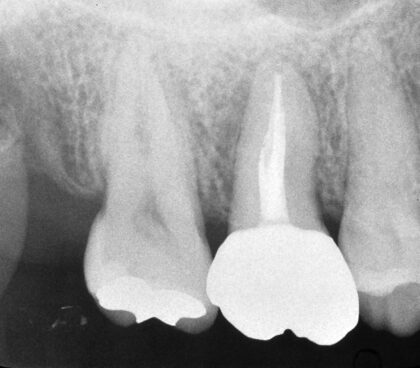

移植前

重度虫歯の右上6番の歯に、右上の親知らず(8番目)を移植しました。

移植後